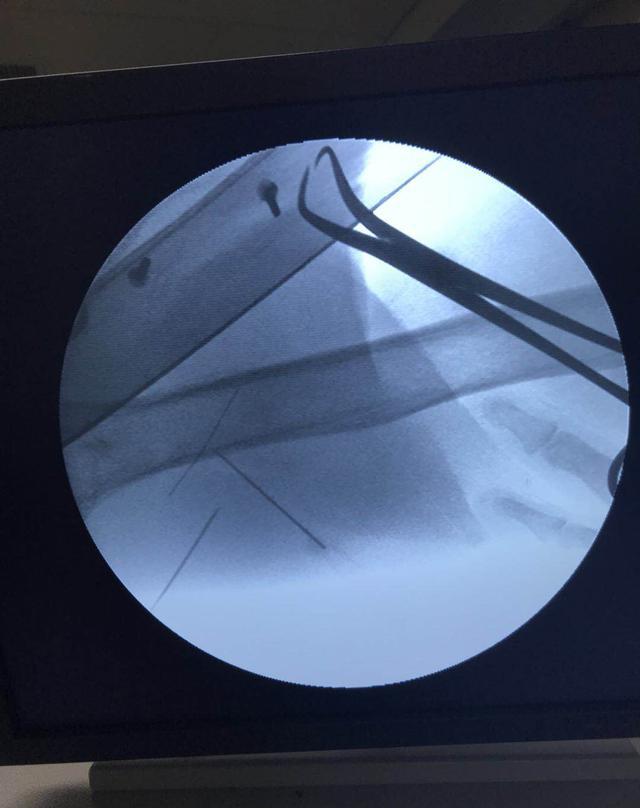

取断针

图片尺寸1080x1439